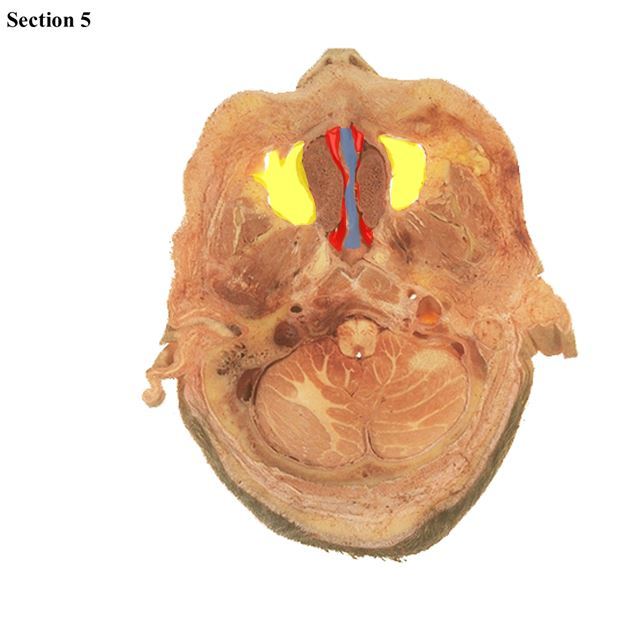

5

Q

The blue structure is the _____

The red structure is the _____

The green space is the _____

A

submandibular salivary gland

epiglottis

laryngopharynx

How well did you know this?